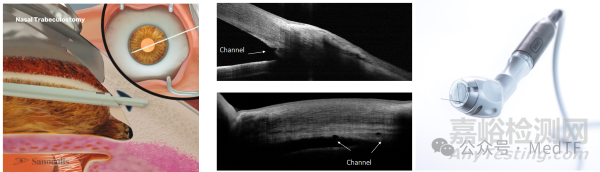

MINT

MINT是在鼻側(cè)小梁網(wǎng)進行多個造口,房水通過通道流入小梁網(wǎng)然后從Schlemm's管排出,從而達到降低眼壓的目的。

MINT采用獨特的機械半自動環(huán)鉆技術,配備尖端0.14mm直徑器械,可在色素性小梁網(wǎng)中創(chuàng)建精準開口。